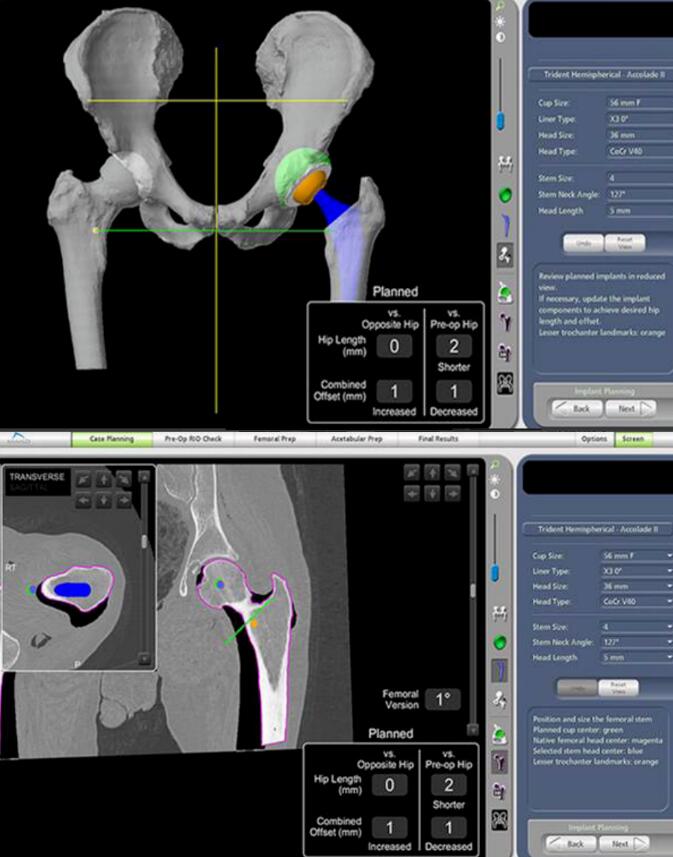

利用患者术前CT数据构建3D骨骼模型,通过导航模块在专属3D模型图像上规划植入物尺寸与摆放位置,对安装效果和截骨量、截骨角度等进行提前“预演”,实现精准术前方案定制。

2、术中:实时动态平衡与智能防错

手术中系统实时捕捉软组织张力,关节面的接触点,髋关节的前倾角,下肢长度,旋转中心,偏心距等临床信息,医生据此调整手术计划,实现关节平衡并达到1度1毫米个性化放置。当操作偏离预设路径0.1毫米,机械臂触发阻力反馈、警报并终止操作。